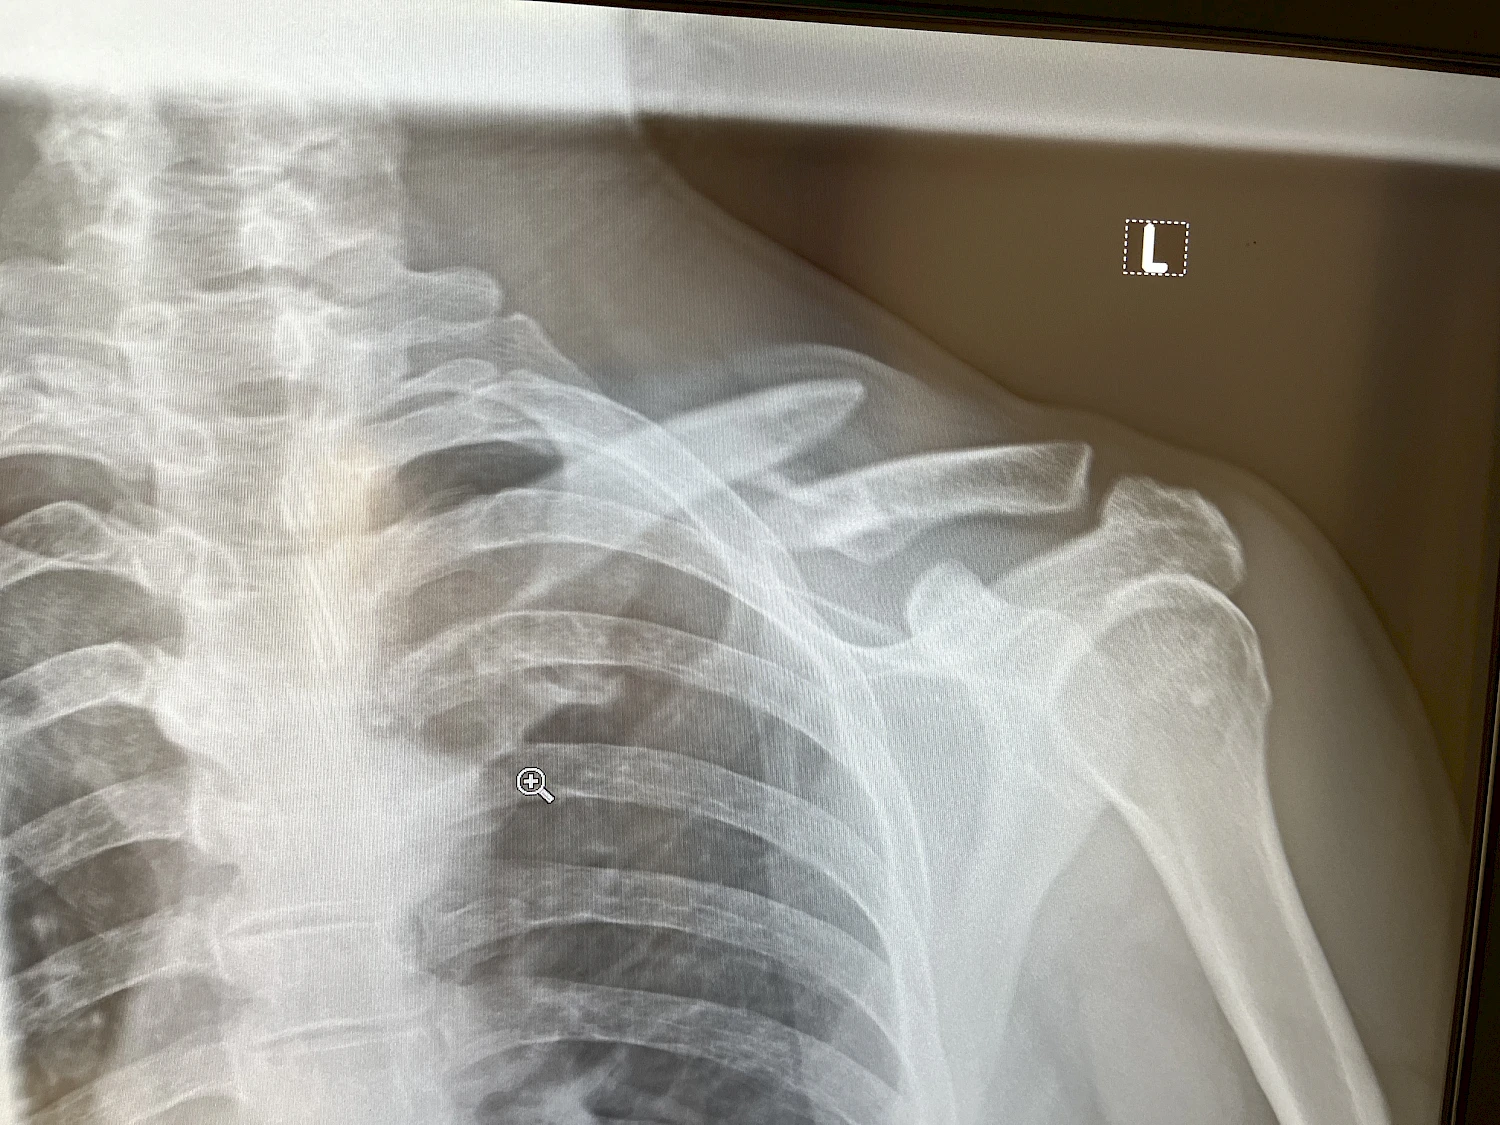

Nous avons dû faire face à une grande variété de blessures. Les motards présentaient souvent des fractures osseuses, des traumatismes thoraciques et des lésions de la colonne cervicale, etc. Quant aux pilotes et copilotes de voitures et de camions, ils avaient surtout des blessures à la colonne vertébrale. Cependant, j’ai été surpris par le nombre d’infections que nous avons dû traiter, probablement liées aux conditions d’hygiène dans le désert et notamment de la poussière.